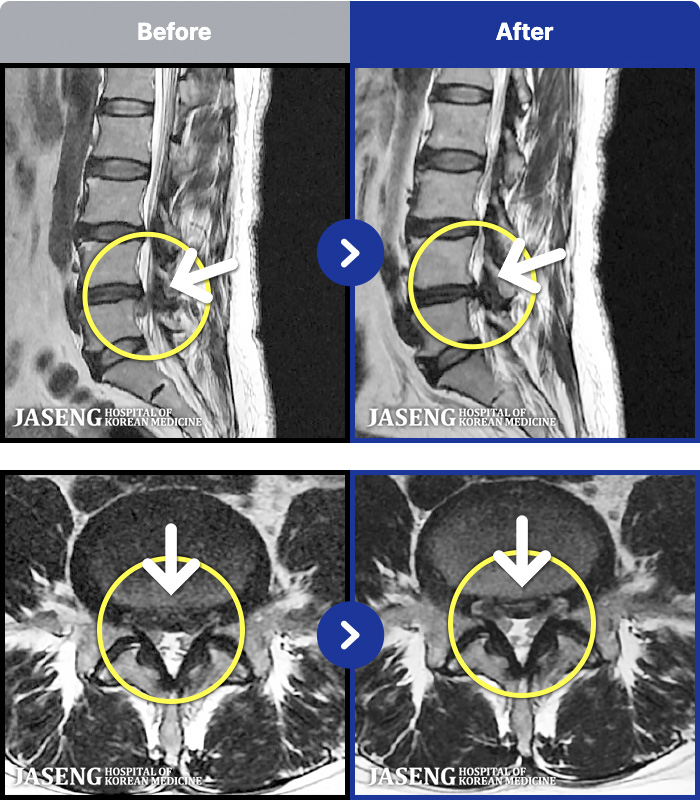

1,237 MRI ũ ʸ Ȯϼ.

1,237